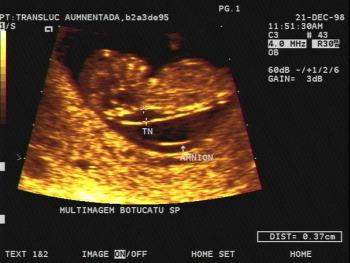

Gynecology Images: Normal Abnormal Obstetric Images: 1st Trimester: Normal Abnormal 2nd Trimester: Normal Abnormal 3rd Trimester: Normal Abnormal Medical Professionals: Upload Your Here Obstetric Images: 3rd Trimester: Normal Normal Thymus - Albana Cerekja Fetal urethra at 31 weeks: just before micturition - Albana Cerekja Normal Female: 4D still image - Effendi Mansoor Monolateral double renal artery,: Normal variant kidney artery supply - Albana Cerekja TRV Fetal Head: BPD and HC Measurements - SIEMENS Velamentosa insertion: 3rd trimester - Effendi Mansoor Umbilical Cord (3D Surface Rendering): Normal Cord - MEDISON SAG Fetal Face, Profile: Fetal Breathing on Color Doppler - SIEMENS 3D Surface Reconstruction: Face - Cayrol Guillermo 3D Surface Reconstruction: Extended Breech Presentation - Saied Mohamed Tohamy 3D Surface Reconstruction: Face - Juan Carlos Pons 3D Surface Reconstruction: Face and Foot - Cayrol Guillermo 3D Surface Reconstruction: Face - Juan Carlos Pons 3D Surface Reconstruction: Face - Juan Carlos Pons